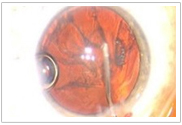

在整個治療、計劃和手術(shù)過程中,可提供整個眼前節(jié)的三維圖像。

手術(shù)醫(yī)生可以在手術(shù)過程中監(jiān)視全部眼前節(jié)

(1)高分辨率的視頻顯微鏡,實時成像

(2)一體化的、廣角的光學(xué)相干斷層

掃描(OCT),三維成像